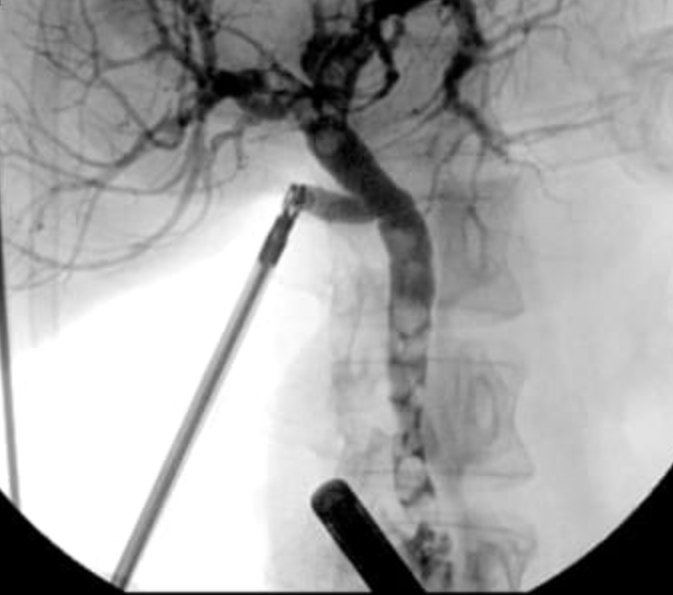

Large submucosal mass in sigmoid.

What are the top THREE things in your differential diagnosis? Comment below.